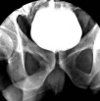

Цистография. Рентгенологический метод исследования, довольно широко используемый в урологии, основан на искусственном контрастировании внутренней полости мочевого пузыря и последующем выполнении рентгенографии. Его можно использовать для визуализации размеров, формы и положения мочевого пузыря, для определения наличия или отсутствия включений в его полости (камни, опухоли). Некоторые модификации этой методики позволяют оценить тонкую структуру слизистой оболочки. Цистография используется для выявления камней в мочевом пузыре, воспалительных или опухолевых изменений в его стенках и отклонений в развитии этого органа. Он производится путем введения различных контрастов в полость мочевого пузыря, существует несколько разновидностей этого метода, различающихся по характеру используемого контраста и способу его введения.

Цистографический метод основан на рентгенологическом исследовании мочевого пузыря после контрастирования его полости или внутренней поверхности. В настоящее время этот метод постепенно вытесняется другими, менее инвазивными диагностическими методами (в основном, ультразвуковым сканированием), но он все еще довольно популярен в современной урологии. Существует несколько типов удаления мочевого пузыря, которые отличаются контрастом внутренней поверхности мочевого пузыря. Наиболее распространенной является восходящая цистография, при которой раствор контрастного вещества вводится через катетер через мочеиспускательный канал в мочевой пузырь.